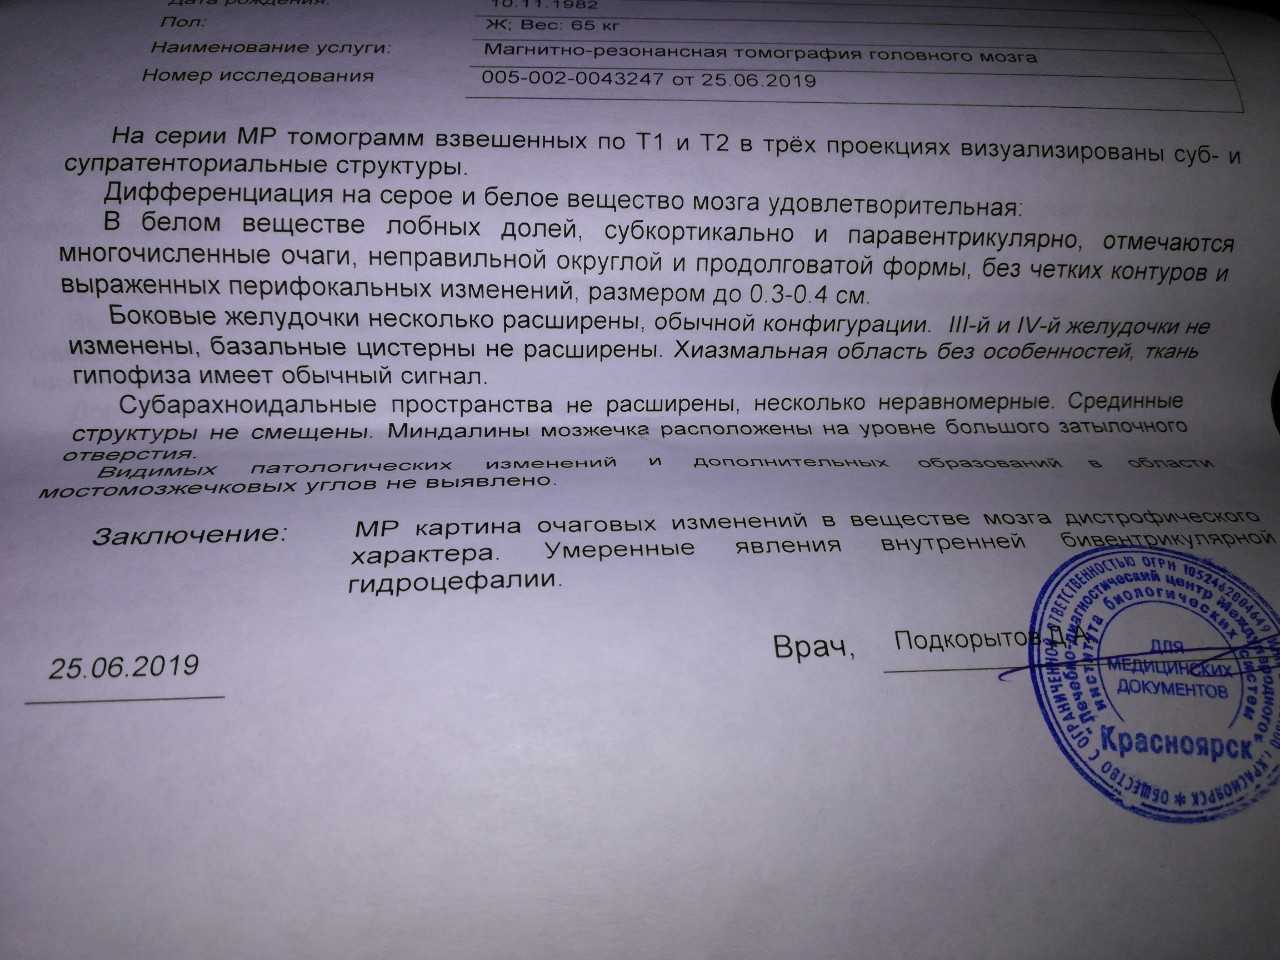

Медицинская диагностика: КТ и МРТ головного мозга